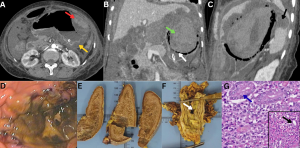

Fig 11: Clinical history:

A 55-year-old diabetic male presented with facial numbness, visual blurring, and acute-onset gait imbalance.

Figures A–C:

Axial diffusion-weighted imaging (DWI), apparent diffusion coefficient (ADC), and FLAIR images demonstrate diffusion restriction with corresponding T2/FLAIR hyperintensity involving the right trigeminal nerve (red arrows), consistent with trigeminal neuritis. Additionally, acute infarcts are noted in the right cerebellar hemisphere, showing DWI hyperintensity with corresponding ADC hypointensity and FLAIR hyperintensity (green arrows).

Figures D–F:

Axial DWI, ADC, and FLAIR images demonstrate diffusion restriction with associated T2/FLAIR hyperintensity involving the right optic nerve (white arrows), consistent with optic neuritis.